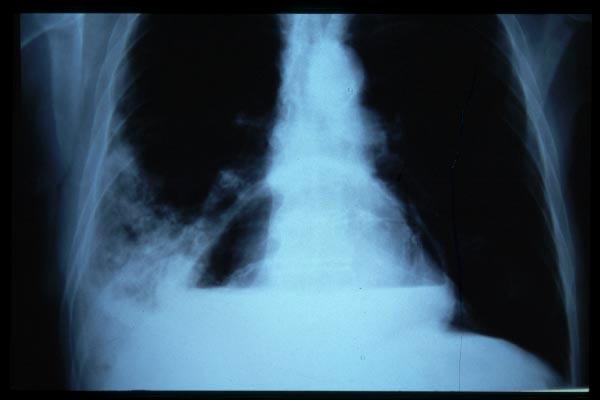

Fibrosis pulmonar. ICC.

Cardiomegalia. ICC.

EAP

APR Insuficiencia cardiaca

Insuficiencia cardiaca.

ICC